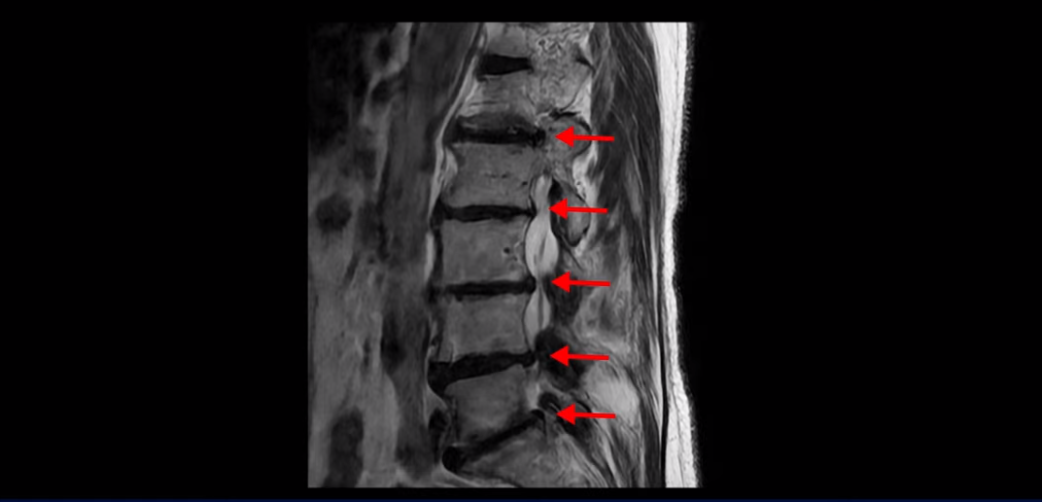

이분 MRI 보시다시피 허리 다섯 마디가 전부 다 퇴행이 심합니다.

특히 4번 5번에는 심한 중심성 협착이 있고,

5번 1번에는 황색인대가 골화되어 왼쪽 신경 나가는 길이 좁아져 있습니다.

그래서 왼쪽 엉덩이와 다리 통증이 더 심합니다. 이렇게 신경 구멍들이 좁아져 있고 신경이 눌리니까 엉덩이와 다리가 너무 저리고 아프고 힘도 빠져서 몇 걸음도 걷기 어려우니까 지팡이를 짚고 저녁에도 아파서 잠을 못 자는 겁니다.